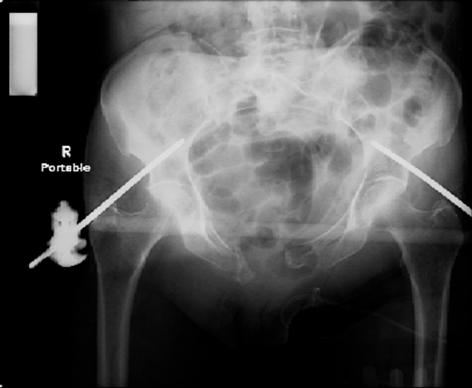

attached are images of a 70 year old female after peds versus car. her own car ran her over.

injuries are limited to the pelvis. left rami open and visible in a 10cm vertical laceration just lateral to left labia majora. wound is grossly clean. no vaginal and no urinary issues. CT scan shows widening of both SI joints anteriorly but I think this is vertically stable pattern.

pt treated that night with I/D and supra-acetabular frame to close the ring. consideration was given for SI screws bilateraly, but given time of night and other factors decision made not to proceed.

so the question is what next operatively if anything? concerns are infection, nonunion anteriorly and possible incompetence of the pelvic floor which may lead to prolapse issues. right rami are comminuted and plating may entail ilioinguinal approach to extend plate laterally to right iliac wing. retrograde screw up right rami is an option but I am not convinced it will add much. adding SI screws very doable, but major concern is restoring anterior ring. so far wound is clean and closed over a drain, and I have no plans to open it back up and wash again.

maintaining pelvic alignment in ex-fix in 70 yo female for any length of time may be challenging.

any thoughts? would anyone plate the pubic symphysis to close the gap and leave the more lateral rami fractures alone? the most recent pelvic case on this website involved pts with suprapubic catheters and antibiotic options including resorbable beads. I wonder how many people would plate and place antibiotic beads. thanks.

attached are several CT cuts. please let me know if you need more. the CT is pre-pelvic ex-fix placement.

Thank you.